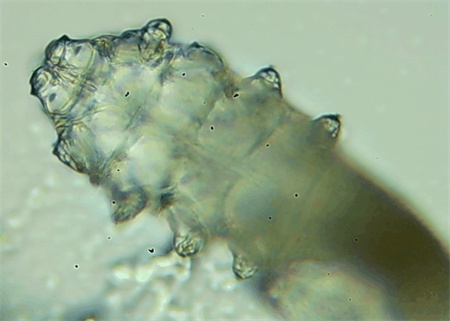

把玻片放到顯微鏡下觀察,通過(guò)電腦實(shí)時(shí)傳送的畫面,可以查看到這些拔下來(lái)的睫毛上是否有螨蟲。

結(jié)果,有6個(gè)人拔下來(lái)的睫毛上都發(fā)現(xiàn)了螨蟲。

這種螨蟲叫做蠕形螨,他們通常呈乳白色、半透明的細(xì)長(zhǎng)狀,擁有四對(duì)腳。它們跟被子上的塵螨可不是同一種。

這些蠕形螨主要寄生在面部、頭皮、眼睛的睫毛毛囊、睫毛皮脂腺,以及瞼板腺里,以睫毛囊上皮細(xì)胞、腺體內(nèi)脂質(zhì)為食物。因此,即使經(jīng)常換洗床單、衣物,也可能會(huì)有蠕形螨。